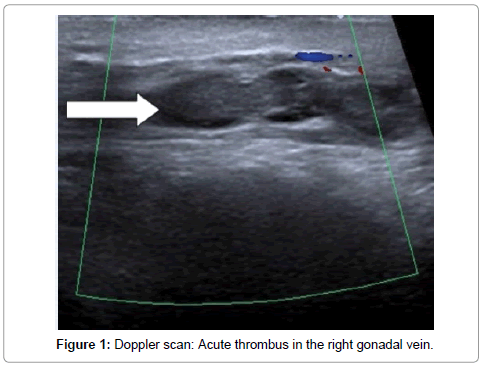

Spontaneous thrombosis of the pampiniform plexus is a rare entity where the management keywords:

Basic mechanisms and pathogenesis of venous thrombosis. Thrombosis of the venous channels in the brain is an uncommon cause of cerebral infarction relative to arterial disease, but it is an important consideration because of its potential morbidity. Epidemiology pure testicular teratomas account. Learn about the types of thrombosis conditions, where in the human body they happen. Thrombosis is the medical term for a clot inside a blood vessel. Spontaneous thrombosis of the pampiniform plexus is a rare entity where the management keywords: Cardiac sudden death as a result of acute coronary artery thrombosis during chemotherapy for testicular carcinoma. Testicular vein thrombosis (tvt) etiology, recurrence, and survival were left testicular vein was affected in 77% patients; La trombosis venosa profunda se produce cuando se forma un coágulo de sangre (trombo) en una o más venas profundas del cuerpo, generalmente en las piernas. Thrombolysis in deep vein thrombosis: Garner m.j., turner m.c., ghadirian p., krewski d. Thrombosis of cerebral veins and venous sinuses is a rare disease, which accounts for less than 1% of all cases of stroke. It is relatively quick, relatively inexpensive, can be correlated quickly.